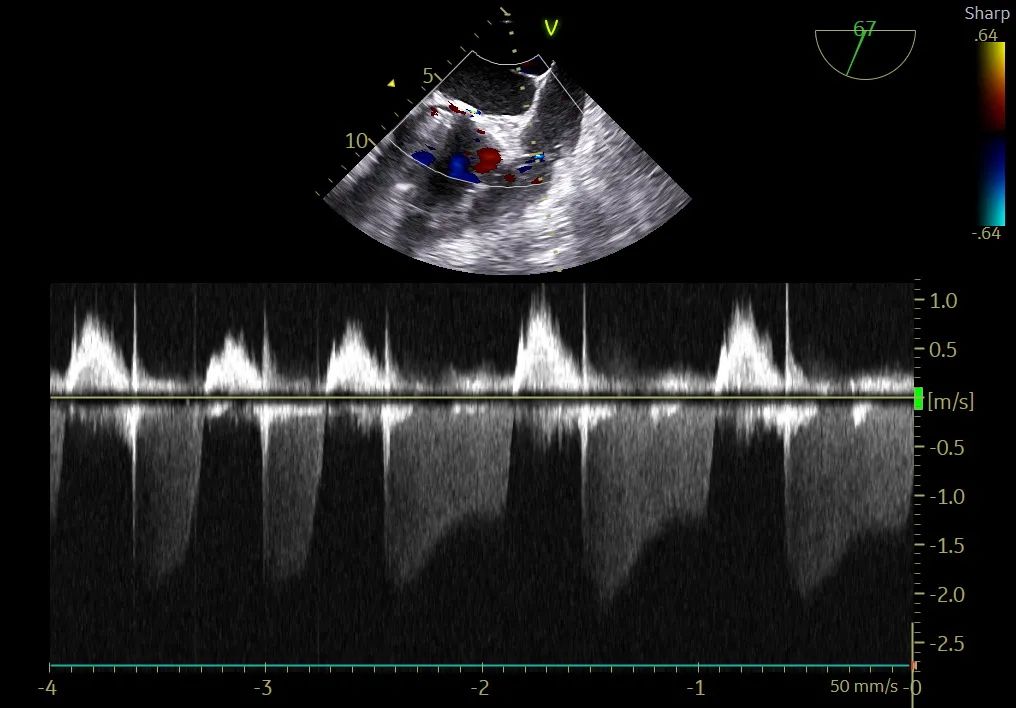

左冠灌注

瓣周漏

术后流速

术中导丝跨瓣后20mm球囊预扩,超声判断冠脉风险尚可,植入L23 VenusA Plus可回收瓣膜位置良好,用23mm球囊后扩支架下缘,微少量瓣周漏。

术后即刻血压135/65mmHg,狭窄解除,释放后超声测量瓣下支架长度6mm标准位释放瓣膜位置完美。整台手术用时不足1.5小时,麻醉、超声等团队全程协作为手术顺利完成保驾护航。